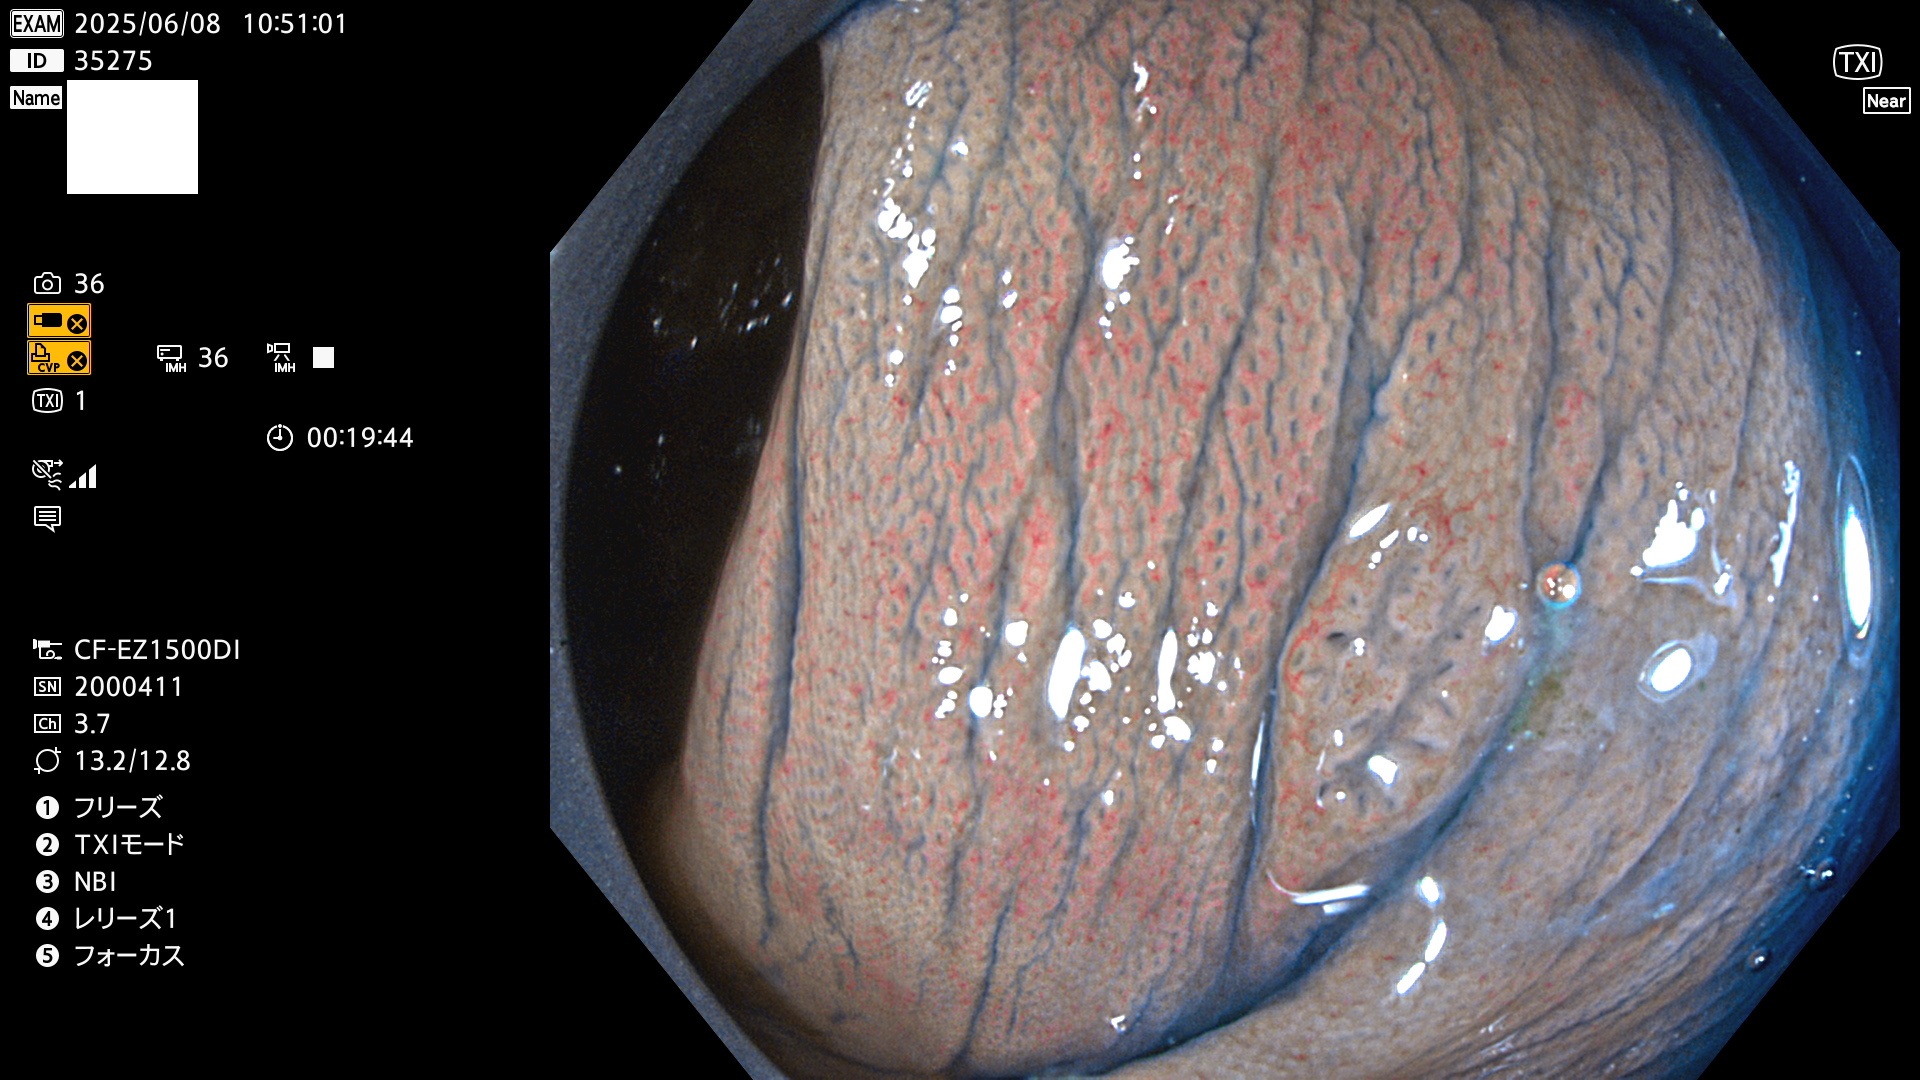

抽出の対象期間 2025年6月5日〜6月8日の4日間(48件の検査)4個 (4/48=8%)